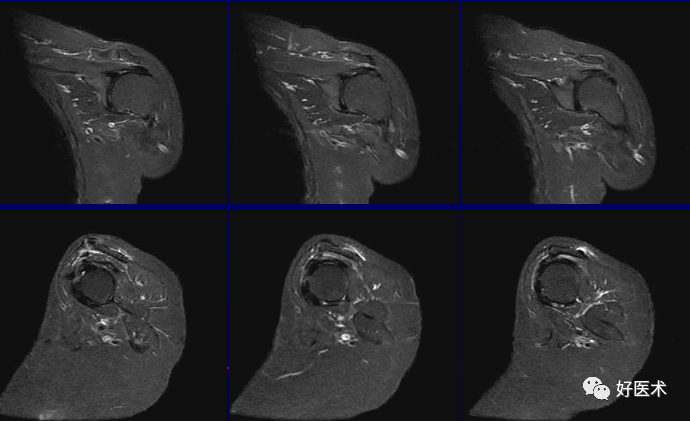

MRI检查技术

(1)体位

仰卧位:检查侧上肢紧贴身体呈中立位或轻度外旋位。

ABER位(前臂外旋外展位):检出关节盂及韧带病变

(2)扫描方位

横轴位:取三维立体定位像的冠状像,扫描层面与关节盂垂直,扫描范围从肩峰至肱骨颈下。

斜冠状位:取横断位作定位像,扫描层面与冈上肌腱平行,扫描范围为锁骨外端至肩峰。

斜矢状位:取横断位作定位像,扫描层面与关节盂平行,扫描范围包括肱骨头和整个关节盂。

轴位:评估Bankart lesions 和盂唇损伤、评估肩胛下肌肌腱。

斜冠状、斜矢状:显示肩袖及冈上肌走行、显示喙肩弓。

斜冠状、轴位:评估盂唇撕裂、肱二头肌长头腱与上盂唇的连接。

轴位:显示肩胛下肌腱撕裂、盂唇撕裂

冠状位:显示肩袖撕裂、盂唇撕裂

矢状位:显示肩袖撕裂、盂唇撕裂